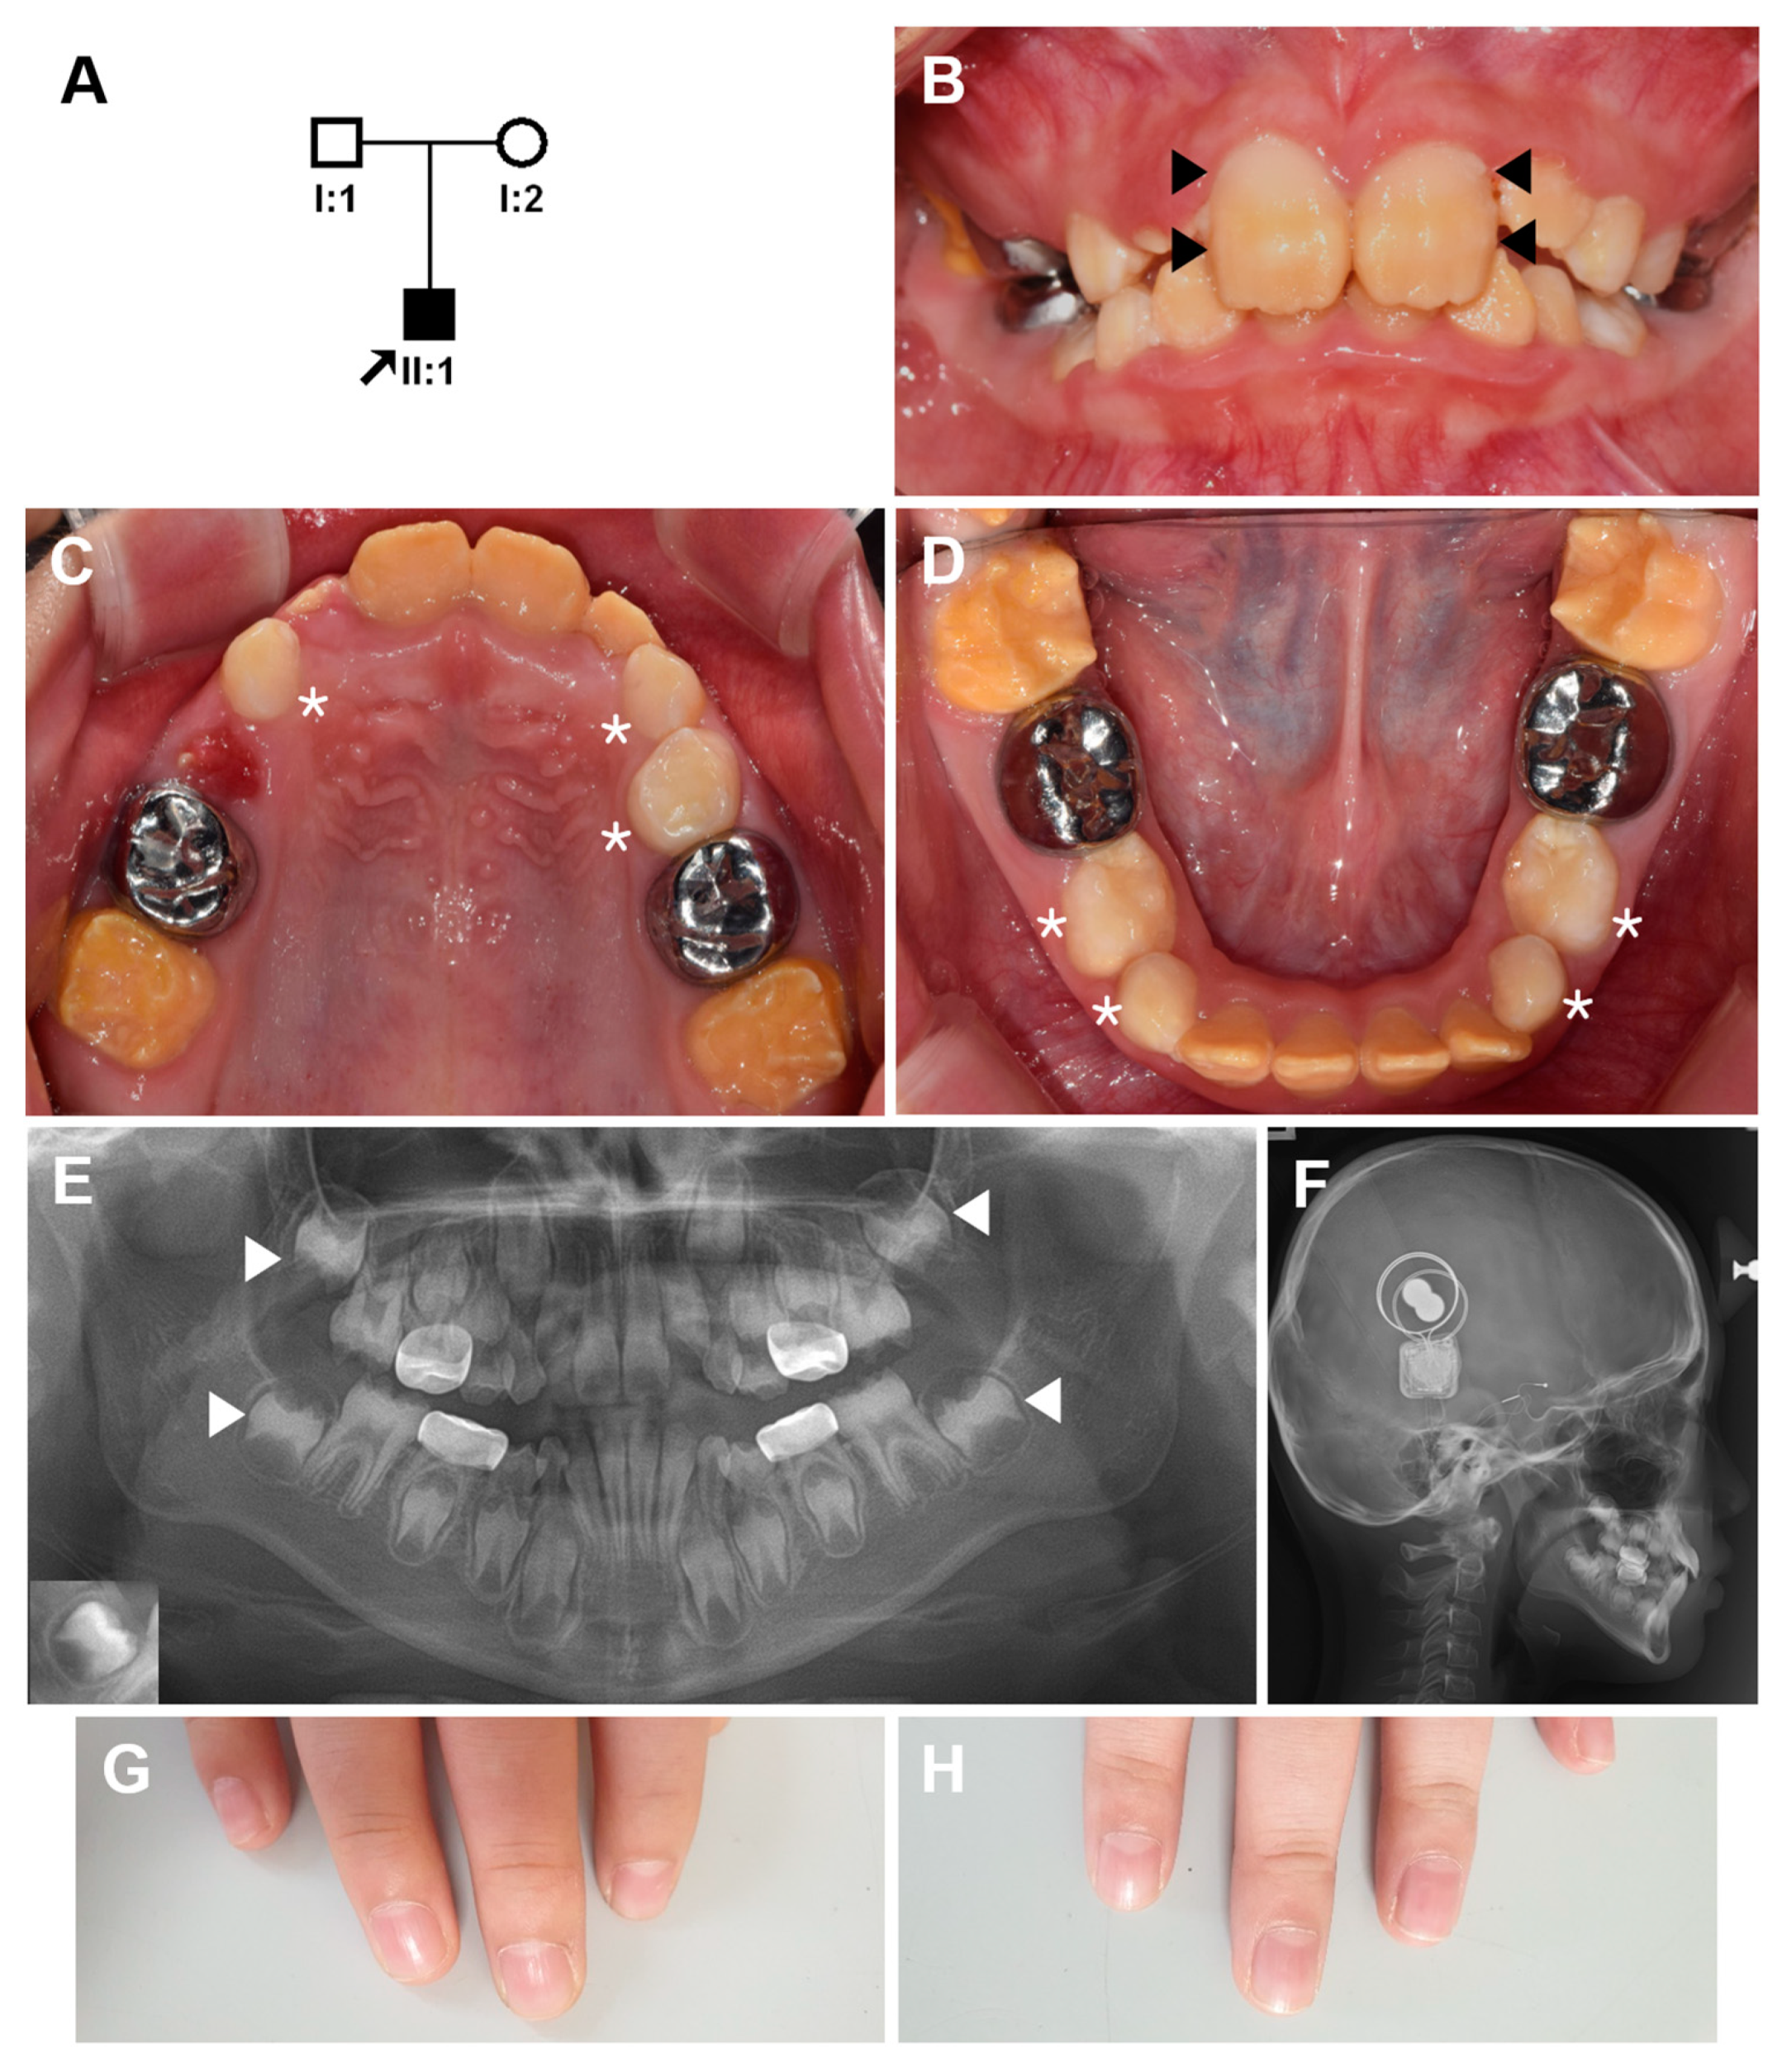

Identification of a Homozygous PEX26 Mutation in a Heimler Syndrome Patient

3. Results